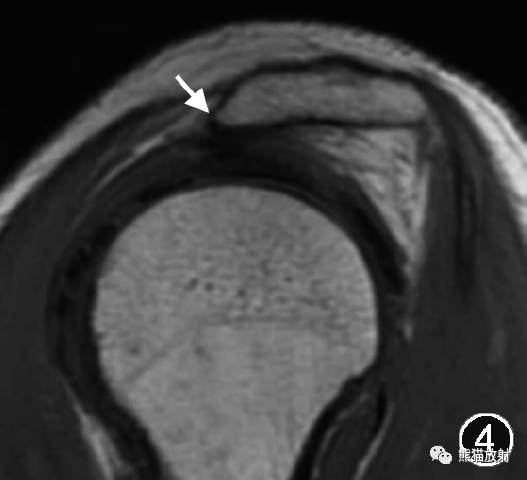

图2,3 Ⅲ型肩峰伴肩峰下撞击综合征的MR图像。肩关节MR平扫斜矢状面

肩峰形态分为4型,Ⅰ型为扁平形,Ⅱ型为弓形,Ⅲ型为钩形,Ⅳ型为凸面向下的反弓形,其中Ⅲ型肩峰最易引起肩峰下撞击(图2,3)。